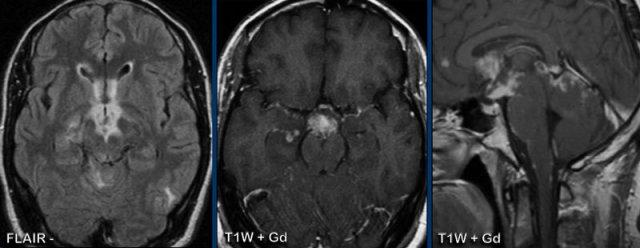

Đây là một ca bệnh tương tự của bệnh nhân có triệu chứng đau đầu và mất thính lực hai bên.

Hình ảnh

Có dày màng cứng kèm ngấm thuốc với hình thái hơi không đều.

Không có ứ máu tĩnh mạch.

Sự ngấm thuốc lan vào ống tai trong (đầu mũi tên vàng).

Tiếp tục với các hình ảnh sau điều trị…

Cùng bệnh nhân trước và 6 tháng sau điều trị steroid với sự thoái lui hoàn toàn các bất thường.

Đây là hình ảnh của một bé trai 9 tuổi được biết có u nguyên bào tủy hố sau.

U nguyên bào tủy biểu hiện là một khối ngấm thuốc lớn (mũi tên).

Có nhiều ổ ngấm thuốc nhỏ là dấu hiệu của di căn màng não mềm.

Tại lần theo dõi sau phẫu thuật và xạ trị, có ngấm thuốc màng não mềm dạng không đều và dạng nốt.

Kiểu ngấm thuốc “phủ đường” này được thể hiện rõ tại cầu não và lớp lót của các bể vallecular.

Khả năng phát hiện các ổ tổn thương và ngấm thuốc màng não mềm có thể được cải thiện bằng cách sử dụng chuỗi xung FLAIR có tiêm thuốc tương phản từ.

Tương tự như trong viêm màng não, cũng cần quan sát khoang dưới nhện trên FLAIR không tiêm thuốc.

Thông thường trên các hình ảnh này, dịch não tủy bị xóa tín hiệu, nhưng trong trường hợp bệnh lý, dịch não tủy sẽ xuất hiện tăng tín hiệu hơn.

Một dấu hiệu hữu ích để phân biệt di căn với viêm màng não là hình ảnh ngấm thuốc dạng nốt dày và sự hiện diện của di căn trong não và màng cứng.

Luôn kiểm tra các dây thần kinh sọ để tìm ngấm thuốc.

Các dấu hiệu lâm sàng và tiền sử bệnh nhân có thể là gợi ý hữu ích.

Đây là bệnh nhân ung thư phổi có biến chứng viêm màng não do ung thư.

Bạn có thể xác định những dây thần kinh sọ nào bị tổn thương không?

Trên các hình ảnh này rất khó nhận thấy, nhưng nếu bạn có thể cuộn qua các lát cắt MRI có tiêm thuốc, bạn sẽ nhận thấy các dây thần kinh sọ sau đây có ngấm thuốc bệnh lý:

- Dây III (mũi tên vàng)

- Dây V & dây VI (mũi tên cam)

- Dây VII & dây VIII (mũi tên xanh dương)

- Dây IX đến XI (mũi tên trắng)

Cũng lưu ý di căn tại cầu não.

Các ví dụ này cho thấy ưu điểm của FLAIR+Gd so với T1W+Gd ở bệnh nhân ung thư phổi có di căn não và viêm màng não do ung thư.

Hình ảnh FLAIR thể hiện rõ hơn ngấm thuốc màng não mềm xung quanh cầu não (mũi tên vàng) và trong các nếp gấp tiểu não (đầu mũi tên đen).